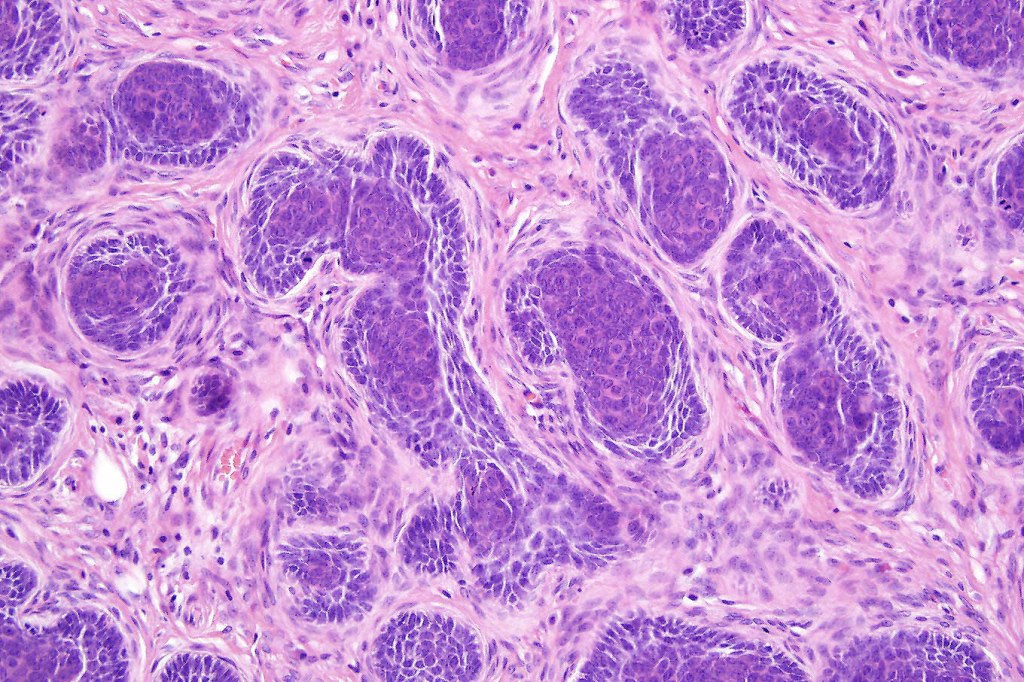

•Variably sized but generally large, basophilic tumor nodules composed of small uniform basaloid cells with minimal cytoplasm

•Variable mitotic activity, can be brisk

•No pleomorphism or abnormal mitoses

•Peripheral palisading but no retraction artifact or stromal mucin deposition

•A rich fibromyxoid mesenchymal stroma with variable papillary mesenchymal bodies (sometimes these are absent)